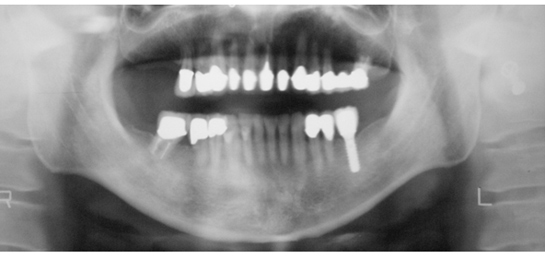

第1大臼歯(奥の大きな臼歯)をインプラント治療で回復した症例

施術前

施術後